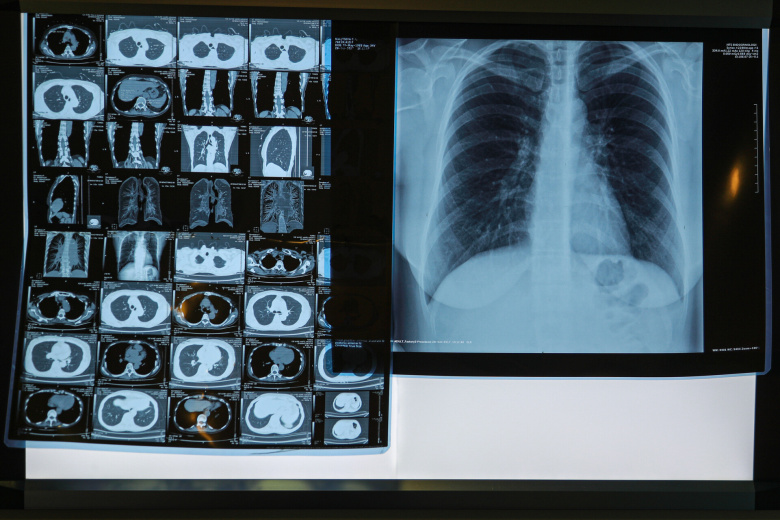

Пульмонолог назвал способы восстановления лёгких после COVID-19

Фото: Сергей Булкин/NEWS.ru

Фиброзные изменения в лёгких — одно из самых неприятных осложнений после коронавируса. Со временем часть повреждений может пройти, при этом решающее значение имеет первый год после болезни. Для скорейшего восстановления врач-пульмонолог, профессор РАН Кирилл Зыков посоветовал полностью отказаться от курения, вакцинироваться от гриппа и пневмококка, пить витамины и заниматься лечебной физкультурой.